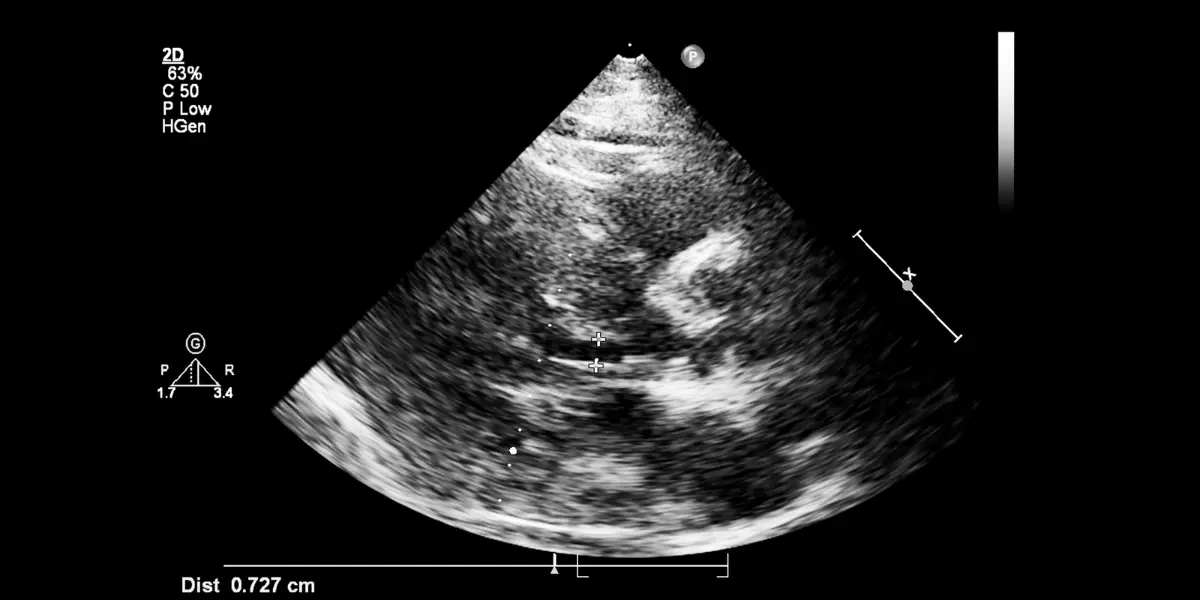

Badanie elastograficzne wykorzystuje się przy pomocy głowicy USG oraz odpowiedniego oprogramowania. Podczas elastografii tarczycy przy pomocy aparatu Alpinion XCube70, diagnosta może ocenić na ekranie dualnym sztywność tkanki. Do dyspozycji pozostaje również podstawowy obraz 2D wraz ze skalą twardości tkanki. Przy pomocy głowicy ultrasonograficznej oraz skali, lekarz ocenia stopień zmian patologicznych.